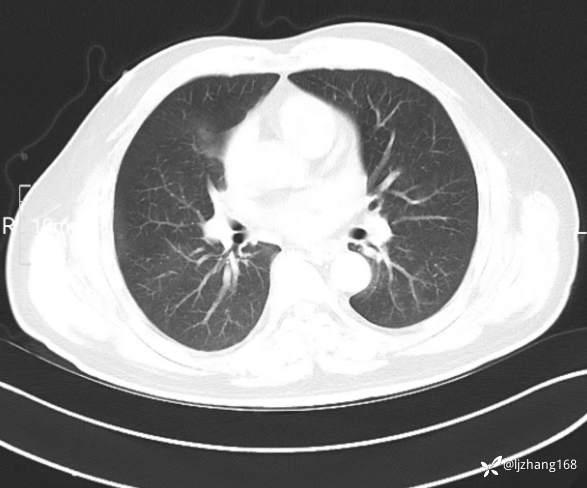

中年男患,右肺团片影,炎症0R肿瘤?

辅助检查:糖化血红蛋白12.3%。肺炎支原体IgG、IgM、呼吸道合胞病毒均未见明显异常。胸部CT:右肺上叶阻塞性肺炎。